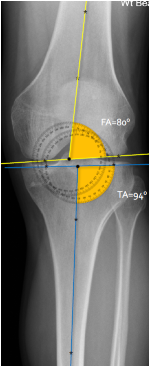

Q what is the top measurement? and what is the average + range?

A: Femoral Angle (Knee)

assesses the lateral angle between the femoral shaft and condyle lines. The average is 81°, with a range of 75-85°.

Q what is the name of the bottom measurement? and what is the average + range?

A: Tibial Angle

assesses the lateral angle between the tibial shaft and plateau lines. The average is 93°, with a range of 85-100°.